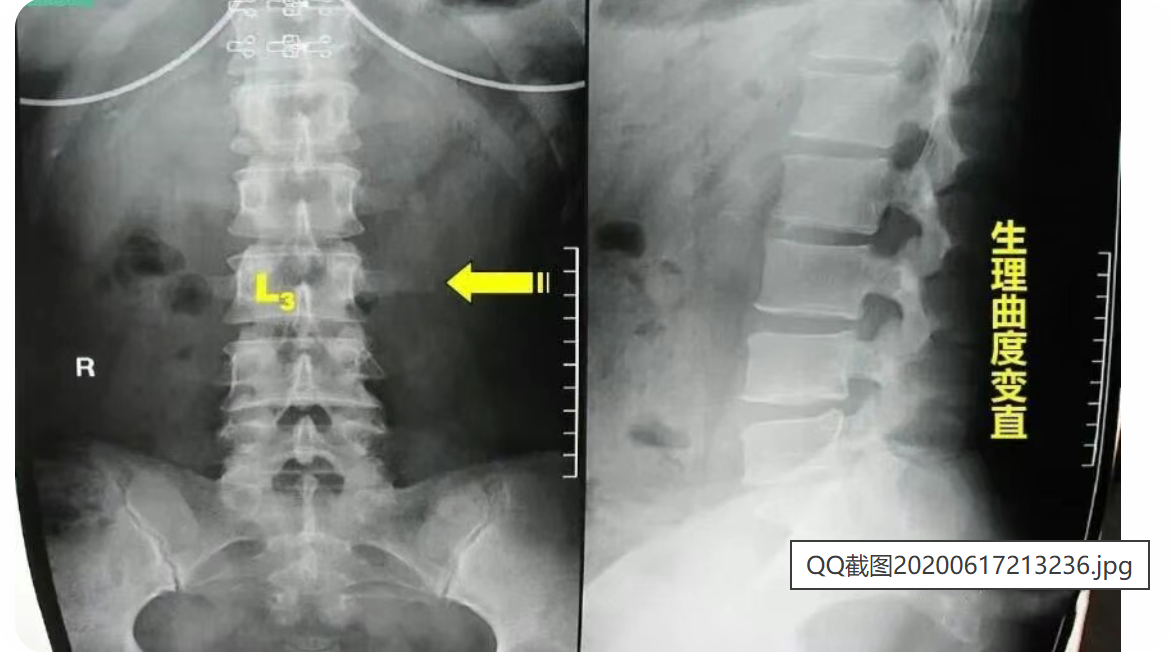

腰椎一共有五个,正常腰椎呈生理性前凸,第3腰椎位于前凸的顶部,腰椎在传导重力时,常是以第3腰椎为其活动中心,故成为腰椎前屈、后伸、左右旋转活动的枢纽。因此,两侧横突所受的牵拉应力最大。在生长发育过程中,受拉应力最大的横突其生长速度也最快。腰三横突位于肋弓与髂嵴之间,横突向后成30度角左右,向前倾斜15度左右,近尖部骨面增厚粗糙。

第三腰椎横突比其他腰椎的后伸曲度大,向侧方延伸最长,位于腰椎中部,两侧腰椎横突联线形成以第三腰椎横突尖为顶点的纵长菱形。第一、二腰椎横突外侧有下部肋骨覆盖,第四、五腰椎横突深居于髂骨内侧,只有第三腰椎横突缺乏肋骨及髂骨保护,因而易受损害。

第三腰椎位于腰前凸曲线之顶点,背阔肌的髂腰部分纤维止于第三腰椎横突,腰大肌的部分肌纤维也止于此处,骶棘肌的一部分肌纤维也止于此,因此,第三腰椎成了腰椎的活动中心,起到了类似接力站的作用,为腰椎屈、伸、侧弯及旋体的枢纽,所受的杠杆作用最大。而第三腰椎横突更是受力点。由于第三腰椎横突较长,以致附着于此处的肌肉、筋膜、韧带能有效地保持脊柱的稳定性及正常的活动。较长的横突又能增强肌肉的杠杆作用,肌肉收缩牵拉机会多,拉力最大,当这些组织异常收缩时,横突末端首当其冲。这种解剖特点构成末端易受损伤的基础,往往因劳损而引起横突末端周围的纤维织炎。横突越长,发病率越高,以单侧多见。